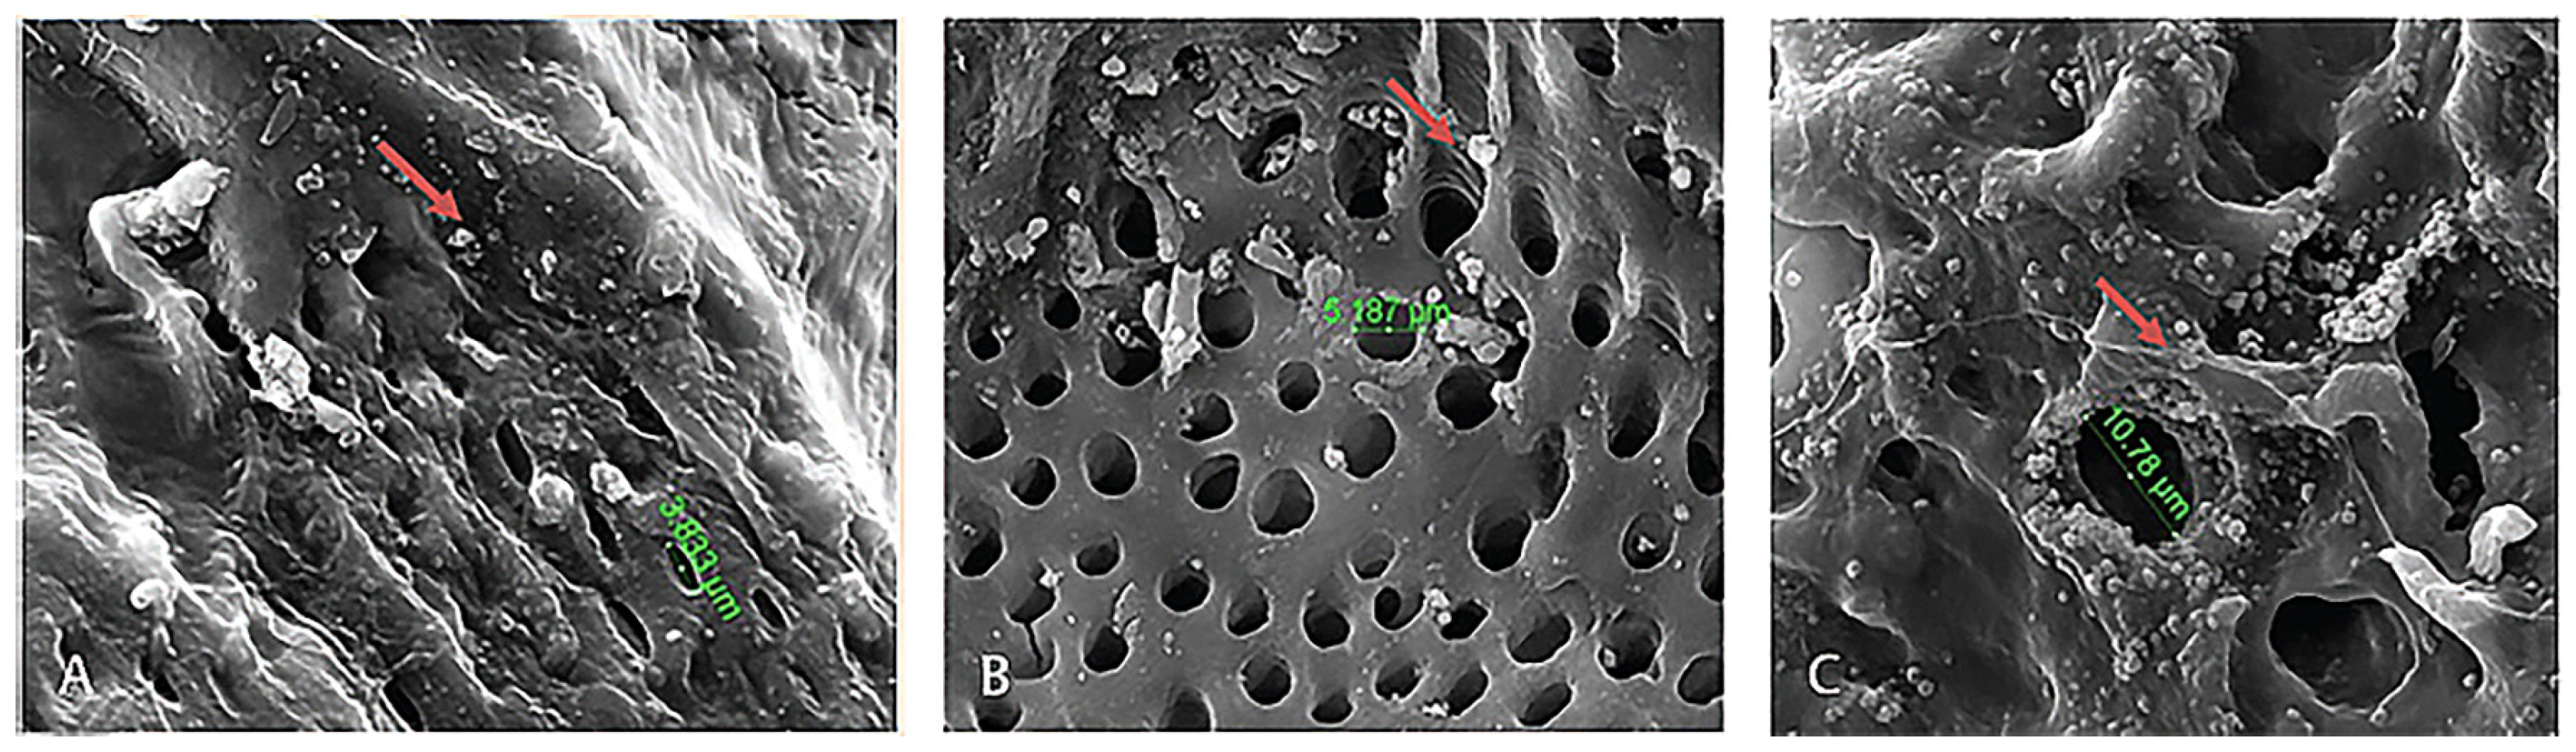

| Ko et al. [227] | AD-MSCs from human | Purchased | Nanostructured decellularized tendon | Rat | 4 mm calvarial defect | Nanostructured scaffolds had advantages over microstructure scaffolds as it enhanced cellular alignment, improving differentiation and regenerative potential of AD-MSCs resulting in accelerated bone regeneration |

| Di Bella et al. [228] | AD-MSCs | Inguinal fat pad | PLA | Rabbit | 15 mm in diameter calvarial defect | PLA coated with fibronectin displayed significantly more bone formation within the scaffold matrix compared to non-coated group. The surface treatment of scaffolds with fibronectin enhances bone regeneration, due to the hydrophilic nature of fibronectin that permits greater cell adhesion, proliferation, and differentiation into the scaffold. |